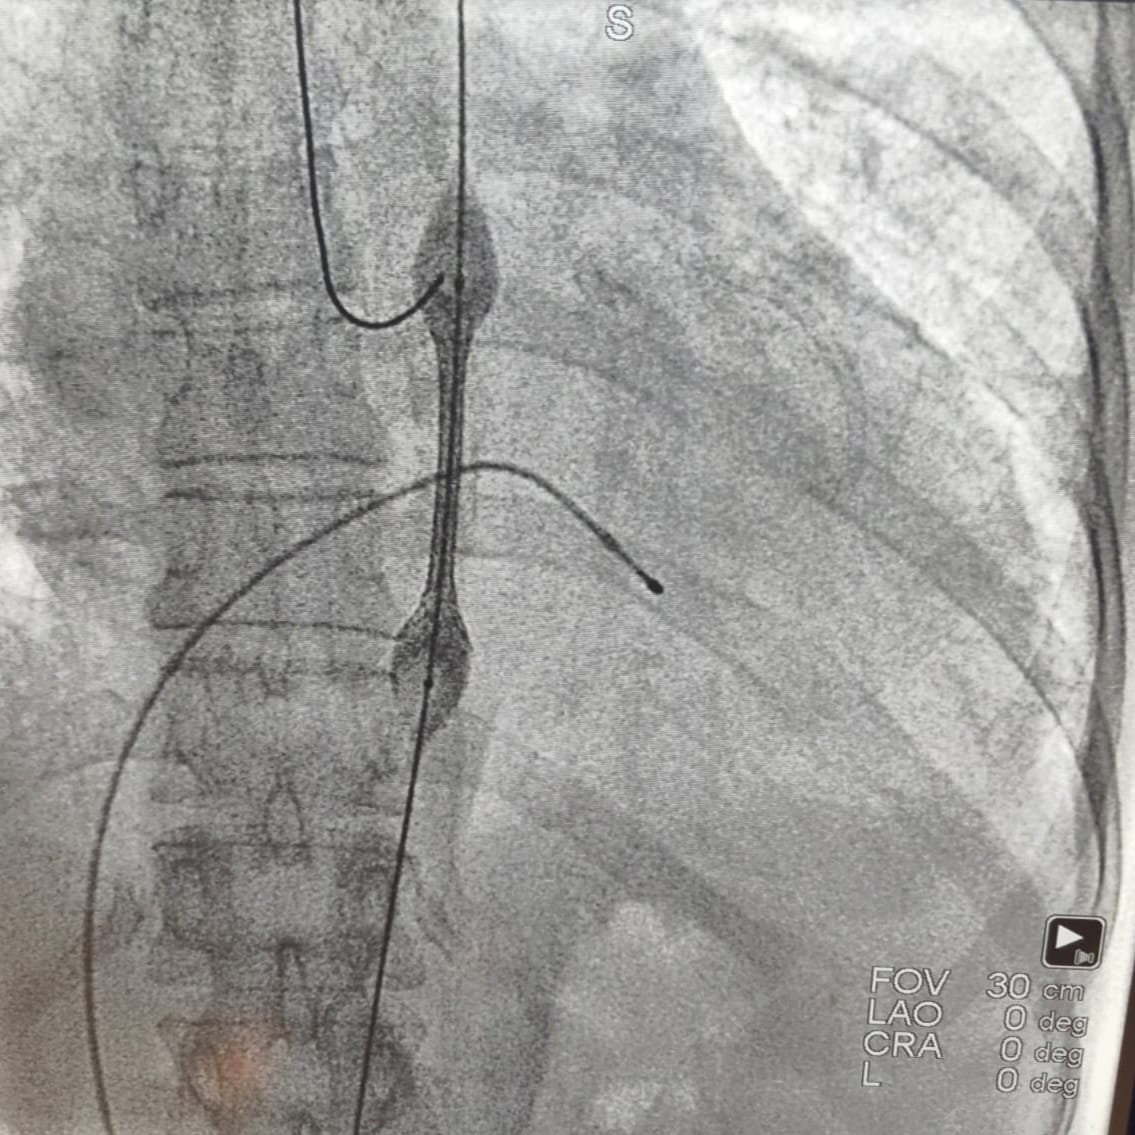

Acil servise başvurmasının ardından hızla anjiyografi ünitesine alınan hastanın işlem sırasında kalbi durdu. Kardiyoloji ekibinin anında müdahalesiyle tıkalı iki damar açılarak kalp ritmi yeniden sağlandı. Ancak aort damarındaki ciddi darlık nedeniyle tansiyon kontrol altına alınamayınca ve solunum sıkıntısı devam edince, endovasküler (kapalı) yöntemle aort koarktasyonu tedavisi uygulanmasına karar verildi.

Gerçekleştirilen ileri düzey girişim sonrasında hastanın tansiyon değerleri normal seviyelere dönerken, nefes darlığı da büyük ölçüde geriledi. Yaklaşık 10 gün süren yoğun tedavi ve takip sürecinin ardından hasta sağlıklı şekilde taburcu edildi.